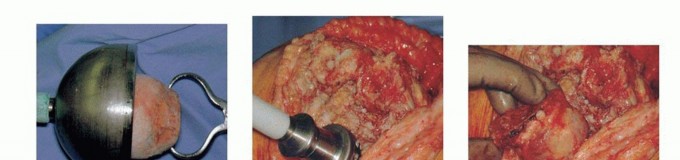

Impaction bone grafting is an excellent technique for managing large, contained metaphyseal defects (Anderson Orthopaedic Research Institute Type 2A and 2B). The technique relies on the viscoelastic properties of tightly packed cancellous bone to provide immediate mechanical stability.

Fresh frozen femoral head allografts are processed through a bone mill to create cancellous chips ranging from three to five millimeters in diameter. The medullary canal is plugged distally, and a trial stem is inserted to maintain the central alignment. The cancellous allograft is then introduced into the metaphyseal voids and vigorously impacted using specialized tamps and a mallet. The impaction process converts the loose chips into a dense, interlocking matrix. This process is repeated until the defect is completely filled and the graft bed is highly resistant to further impaction. The final revision tibial component is then cemented over the impacted graft, utilizing a diaphyseal stem to protect the graft from excessive shear forces during the biological incorporation phase.